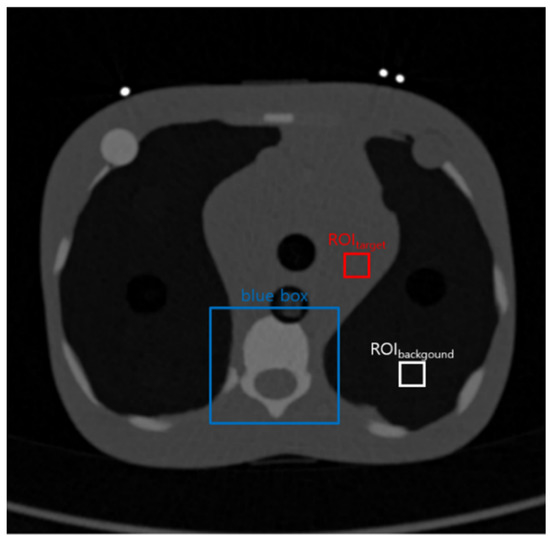

A 5-year-old phantom (Model ATOM 704, CIRS Inc., Norfolk, VA, USA) was scanned using a 64-detector row scanner (SOMATOM Definition AS+, Siemens, Malvern, PA, USA). The CT examination parameters were set as follows: tube potential, 120 kVp; tube current, 23 mA; exposure time, 300 ms; and slice thickness, 1 mm. Then, the axial image of 512 × 512 size was obtained. Generally, the low-dose CT examinations are performed with 30–50 mAs. However, in this study, the parameters of 7 mAs were set in order to show that the FNLM denoising algorithm was efficient at low exposure conditions. Moreover, in modern CT examination, the automatic current technique has been utilized to compensate the differences of thickness of body. However, in this examination, the fixed current was utilized to show the clear results by excluding some random parameters. In this experiment, we did not add the Gaussian noise to the image that we obtained to derive practical results from an unaffected condition. Figure 2 shows the initiative image of the 5-year-old phantom. The ROIs and blue box in the image were set as the similar regions to the image of the MASH phantom.

Figure 2.

The image obtained from a 5-year-old phantom. The region inside the blue box was magnified to compare the denoised images. ROIs were set to calculate the coefficient of variation (COV) and contrast-to-noise ratio (CNR) of the chest image.